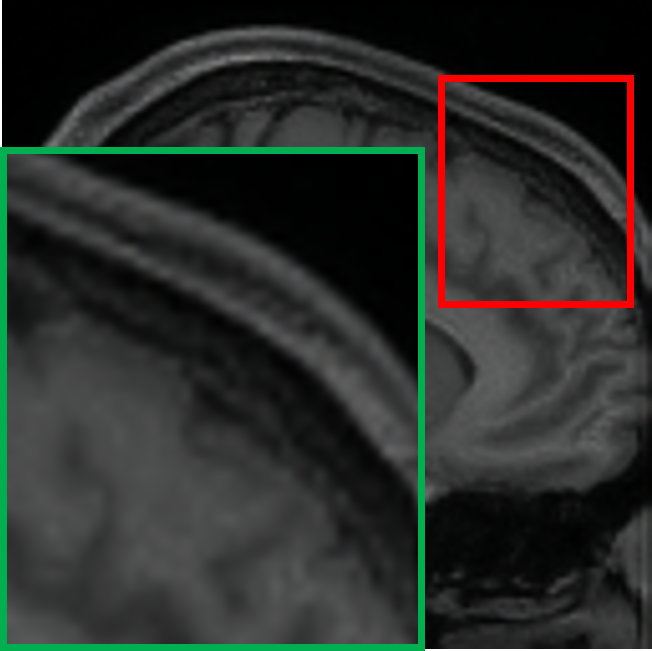

IV-C Visualization of the expert specialization

To further elucidate the functional specialization of each expert within the proposed MoE framework, we visualize the difference maps between each expert’s output and the ground truth 7T MRI. These maps are computed by taking the pixel-wise absolute difference between the expert output and the ground truth 7T MRI, highlighting the residual discrepancies and reconstruction focus of each expert. In the visualizations, lighter areas reflect lower reconstruction errors, suggesting better alignment with the ground truth. As shown in Fig. IV, each column represents the output of a particular expert, visualized through its corresponding absolute difference map with respect to the 7T reference. The final output is computed via a weighted combination of expert outputs. The visualized difference maps underscore the distinct specialization of each expert. Specifically, Expert 1 exhibits minimal residuals in homogeneous white matter regions, preserving large-scale anatomical continuity. Its low-frequency focus is evident in the smooth residual patterns and coherent structural boundaries. Expert 2 demonstrates heightened sensitivity to cortical regions and sulcal boundaries, with pronounced residual suppression around edges and high-frequency details. Expert 3 shows enhanced reconstruction accuracy at tissue interfaces and transitional zones. The residuals are particularly reduced in regions of sharp contrast changes. These observations confirm that each expert effectively targets specific anatomical and textural characteristics, guided by their unique architectural and loss function design. The gating mechanism further facilitates optimal integration by adaptively weighting expert contributions according to the local image context, thus ensuring a globally coherent and anatomically faithful 7T-like reconstruction.

TABLE IV: Visualization of the expert specialization

E1subscript𝐸1E_{1}italic_E start_POSTSUBSCRIPT 1 end_POSTSUBSCRIPT E2subscript𝐸2E_{2}italic_E start_POSTSUBSCRIPT 2 end_POSTSUBSCRIPT E3subscript𝐸3E_{3}italic_E start_POSTSUBSCRIPT 3 end_POSTSUBSCRIPT Final

[Uncaptioned image] [Uncaptioned image] [Uncaptioned image] [Uncaptioned image]

𝒢1=0.21subscript𝒢10.21\mathcal{G}_{1}=0.21caligraphic_G start_POSTSUBSCRIPT 1 end_POSTSUBSCRIPT = 0.21 𝒢2=0.48subscript𝒢20.48\mathcal{G}_{2}=0.48caligraphic_G start_POSTSUBSCRIPT 2 end_POSTSUBSCRIPT = 0.48 𝒢3=0.31subscript𝒢30.31\mathcal{G}_{3}=0.31caligraphic_G start_POSTSUBSCRIPT 3 end_POSTSUBSCRIPT = 0.31 Weighted

• *

The expert-specific weights (𝒢1subscript𝒢1\mathcal{G}_{1}caligraphic_G start_POSTSUBSCRIPT 1 end_POSTSUBSCRIPT, 𝒢2subscript𝒢2\mathcal{G}_{2}caligraphic_G start_POSTSUBSCRIPT 2 end_POSTSUBSCRIPT, 𝒢3subscript𝒢3\mathcal{G}_{3}caligraphic_G start_POSTSUBSCRIPT 3 end_POSTSUBSCRIPT) for this particular slice are dynamically computed by the gating network 𝒢𝒢\mathcal{G}caligraphic_G.